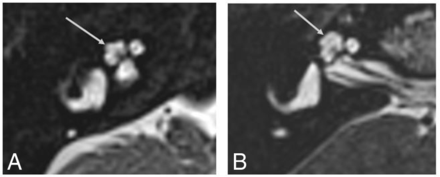

MR imaging of the brain demonstrated bilateral cataracts and cerebellar atrophy. A high-resolution 3D heavily T2-weighted sequence of the IAC revealed symmetric subtle cochlear abnormality characterized by a peculiar appearance of the upper part of the cochlea with an extra half-turn beyond the apical turn, resulting in >3 turns total (Fig 1A).7 The apical turn and the extra half-turn were not pointed but were smooth and flat like a normal apical turn. The cochlear height, measured in accordance with described methods in the literature (Fig 1B), was 6 mm (above the normal range of 4.3–5.4 mm).8,9 The cochleovestibular nerves were present and normal in course and caliber. The other inner ear structures were normal as well, including preserved internal partitioning of both cochleae.

A, High-resolution 3D heavily T2-weighted MR images of the inner ear and IAC in a patient with a TKFC-related disorder. There is an extra turn (arrows) at the apical portion of the cochlea beyond the usual apical turn and an overall greater cochlear height. The cochlear nerves are present, the modiolus is normal in appearance, and there is normal internal partitioning. Contrast this appearance with that of the normal cochlear apical turn seen in Fig 3B, without an extra turn beyond it. B, Coronal CT image through the cochlea shows the method to measure cochlear height as defined by Shim et al:8 The maximal height of the cochlea is measured along an axis perpendicular to the oval window (white line).